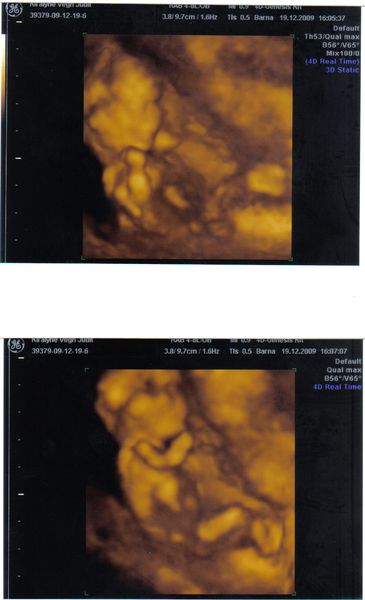

Tegnap délután még bepofátlankodtam a Genesisbe 4D-re, ma 3-ra kaptam időpontot, mert a szülésznőm mondta, hogy ilyen pocsék eredménynél kellene hogy látszódjon valami az uh-on. Nagyon rendik voltak, rögtön adtak időpontot (mondanom sem kell, hogy a fehérváriak elzargattak a kórházban hogy menjek vissza majd ha idősebb leszek, meg hogy az csak szórakoztatás céljára van)szívesen fogadtak és nyugtatgattak a telefonban is.

45 perces alapos uh és többszöri mérés után azt mondta a szonográfus csaj, hogy semmilyen down kórra utaló jelet nem lát a babán. Megvolt a nózija, a tarkóredő is ok a korhoz képest, ujjpercek is rendben vannak. Ez jó, egy kicsit nyugodtabb vagyok, de ettől függetlenül mindenképpen el fogok menni genetikára és megcsináltatom az amniot, mert nagyon sok más rendellenesség van amit az uh nem mutat ki.

Amúgy babácskám nagyon jól érezte magát, először aludt, majd addig maceráltuk amíg felébredt és össze vissza forgolódott, az arcát meg állandóan eldugta a méhlepénybe. 11,2 cm hosszú fejtől talpig és 97 g a súlya.

És nagyon úgy néz ki, hogy kislány. 80%-ra mondta a nő. És én is láttam a 3 csíkocskát ami a szeméremajkakat mutatja.

Íme egy kép a mi kis csontkollekciónkról.